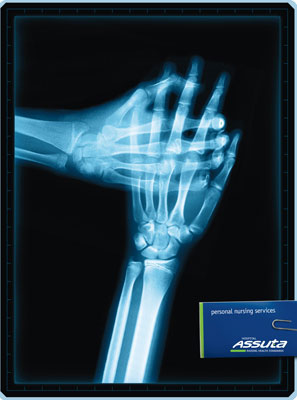

Assuta: X-ray

Personal nursing services: